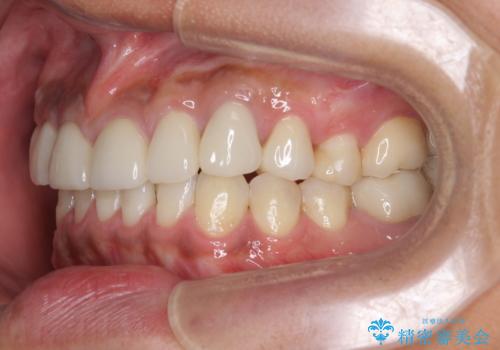

治療について

歯並びを整えたことで、歯ブラシのしやすさが向上し見た目も銀歯を全て除去したことで大きく改善して大変満足いただくことができました。